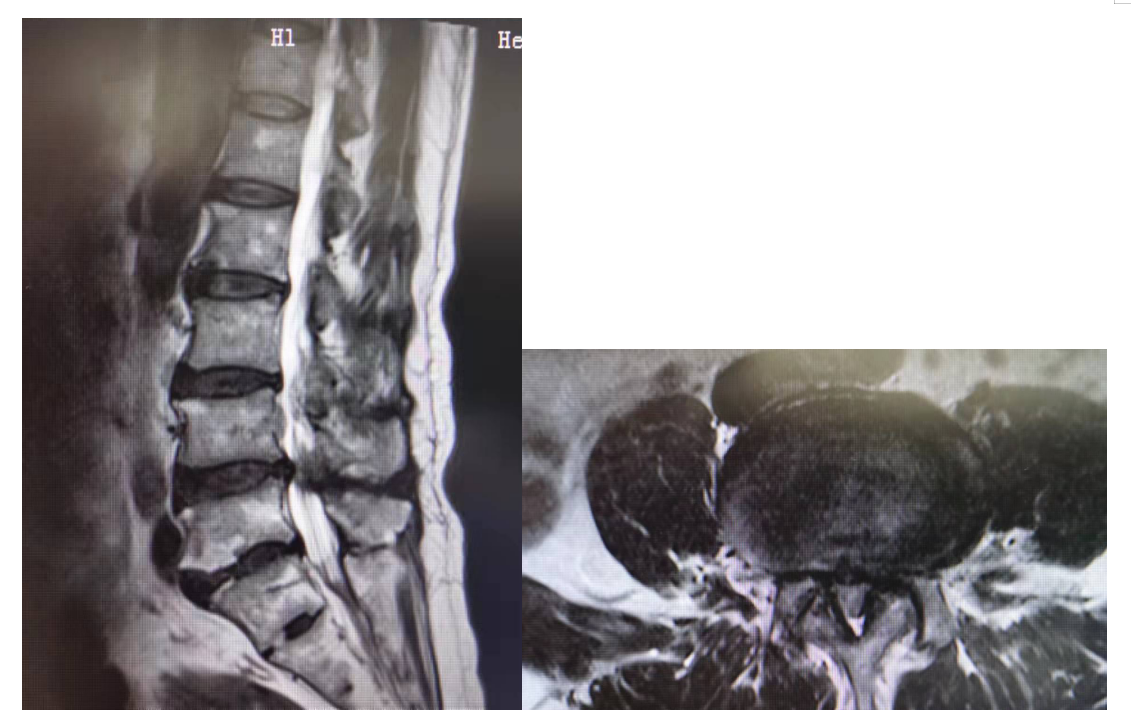

主诉:腰部疼痛3年,加重伴双下肢疼痛麻木1年

现病史:3年前出现腰部疼痛、酸困,无下肢疼痛麻木不适,弯腰活动受限,行走及站立时疼痛加重,平卧休息稍减轻,未治疗,上述症状持续加重,近1年来又出现双下肢疼痛麻木,以左侧为著,步行困难,步行能力约100米,为求诊治,现来我院,遂以“腰椎管狭窄症”为诊断收住我科。发病以来,饮食正常,睡眠一般,体力正常,大小便正常。